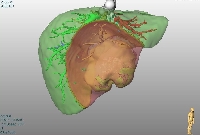

Πρόκειται για άνδρα ασθενή 44 ετών, ο οποίος υποβλήθηκε σε αξονική τομογραφία άνω κοιλίας στα πλαίσια διερεύνησης επιγαστραλγίας. Βρέθηκε μάζα στο 4ο, 5ο και 8ο ηπατικό τμήμα (εικόνα 1). Δε διαπιστώθηκαν σημεία κίρρωσης. Η διερεύνηση για πιθανή πρωτοπαθή εστία εκτός ήπατος ήταν αρνητική. Τέθηκε η διάγνωση της πρωτοπαθούς ηπατικής μάζας (HCC vs CCa). Η εικονική αριστερή εκτεταμμένη ηπατεκτομή με ανάλυση MEVIS (εικόνα 2) οδήγησε σε ηπατικό κολόβωμα μεγέθους 30% του αρχικού, ποσοστό που κρίθηκε ανεπαρκές. Η εικονική κεντρική ηπατεκτομή με ανάλυση MEVIS (εικόνα 3) οδήγησε σε ηπατικό κολόβωμα μεγέθους 65% του αρχικού, ποσοστό που κρίθηκε ικανοποιητικό. Για το λόγο αυτό, ο ασθενής υποβλήθηκε σε κεντρική (parenchymal sparing) ηπατεκτομή (εικόνα 4). Tο παρασκεύασμα αποτελούνταν από τα ηπατικά τμήματα 4b, 5, 8- και τη χοληδόχο κύστη (εικόνα 5). Η διατομή του (εικόνα 6) ανέδειξε μάζα μεγέθους 9 εκατοστών με κάψα, η οποία αφαιρέθηκε άθικτη. Τα ιστολογικά χαρακτηριστικά του όγκου (CK7+, CK19+, CK20-) ήταν συμβατά με CCa (mass forming). Ο ασθενής έλαβε εξιτήριο τη 10η μετεγχειρητική ημέρα.